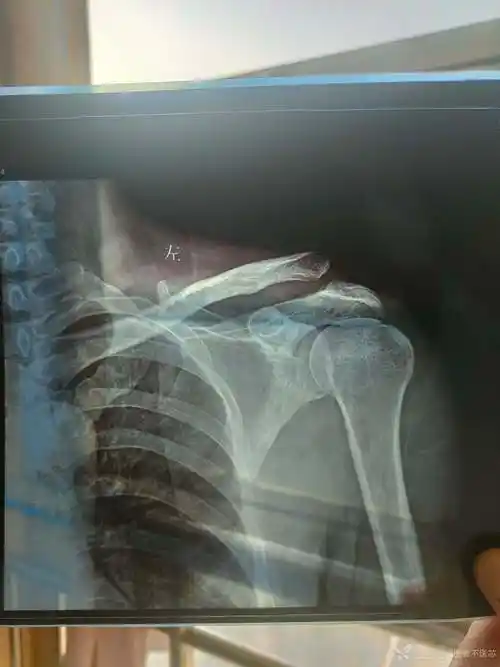

肩关节半脱位

女子3年内肩关节脱位20多次医生取自体髂骨为其根治